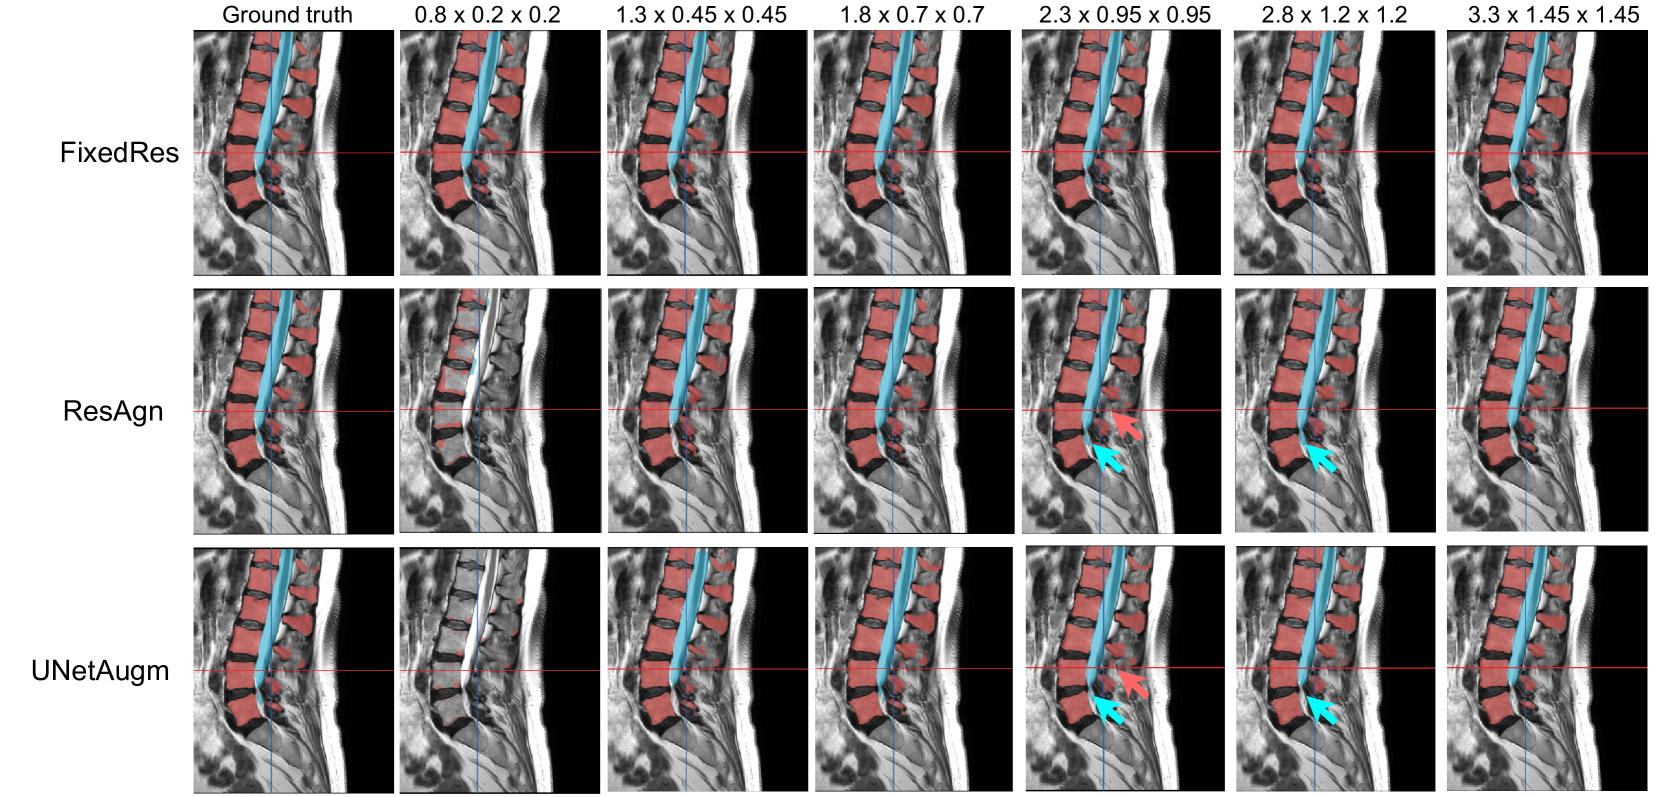

Figure 7: Visualization of vertebrae   and spinal cord   segmentation on the SPIDER dataset obtained from different working resolutions

Refer to caption